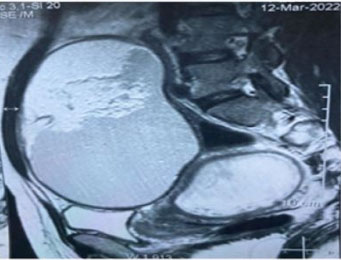

Pelvic ultrasound revealed a large homogeneous hyperechoic abdomino-pelvic mass of 15×15 cm in an evolving single-fetal pregnancy of 16 weeks (Figure 1). Tumor markers were normal levels. The pelvic and abdominal MRI confirmed the presence of an abdomino-pelvic mass partitioned under the umbilical, well encapsulated, 16 cm in long axis, of probable ovarian origin with three components, tissue, fatty and calcium, evoking a germ cell tumor of the immature teratoma type classified 0’Rads 4 (Figure 2).

Figure 2: Abdomino-pelvic mass below the umbilical, well encapsulated with a long axis of 16 cm of probable compartmentalized ovarian origin with three components, tissue, fat and calcium, evoking a germ cell tumor of the immature teratoma type classified 0’Rads 4.